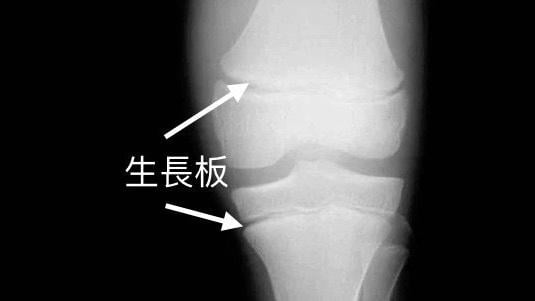

生長板

• 生長板